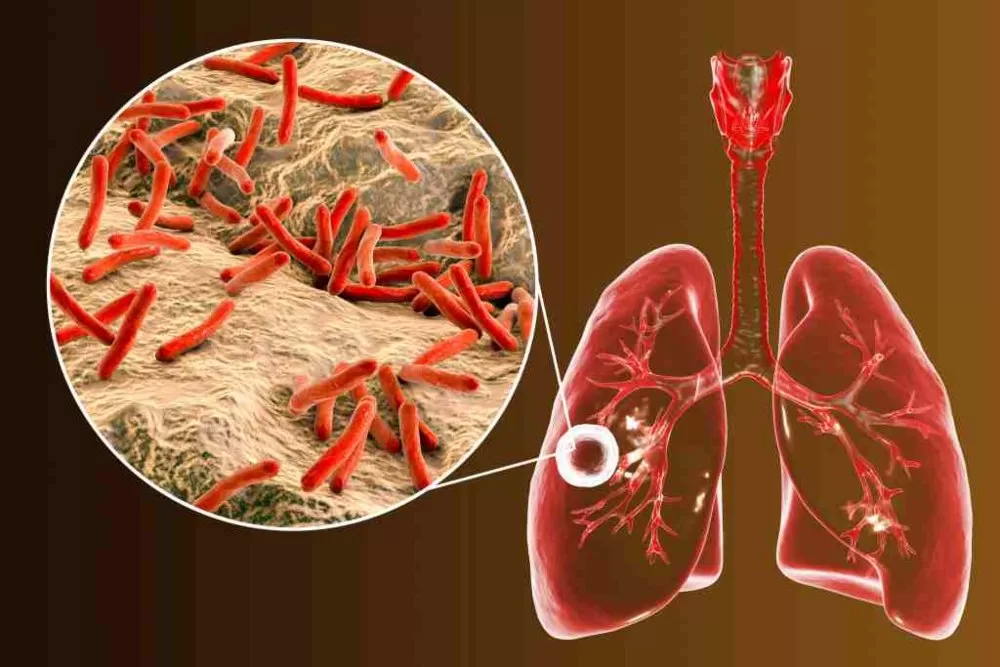

2. Tuberkulosis (TBC)

Tuberkulosis atau TBC merupakan penyakit spesifik yang disebabkan oleh bakteri Mycobacterium tuberculosae. Bakteri ini dapat menyerang semua organ tubuh, tetapi yang paling sering adalah paru-paru dan tulang.

Penyakit TBC menyebabkan proses difusi oksigen yang terganggu karena adanya bintik-bintik kecil pada dinding alveolus. Keadaan ini menyebabkan peningkatan kerja sebagian otot pernapasan yang berfungsi untuk pertukaran udara paru-paru, mengurangi kapasitas vital dan kapasitas pernapasan, mengurangi luas permukaan membran pernapasan, yang akan meningkatkan ketebalan membran pernapasan sehingga menimbulkan penurunan kapasitas difusi paru-paru.